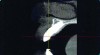

Implant related complications may be classified as minor, intermediate, major reversible/nonreversible, or major nonreversible. For example, a simple complication like a fractured abutment screw is usually considered a minor complication. It usually can be corrected with minimal cost, time, pain, and inconvenience. Treatment may be more involved for an intermediate complication such as a fractured implant (Figure 1). Up the severity scale are major complications, such as when an implant migrates into the sinus2 (Figure 2), or is exposed by mucosa and bone loss and visible to the patient a year after restoration (Figure 3 and Figure 4). Major complications may cause irreversible damage and/or require multiple procedures to try to make the patient “whole,” adding cost, time, pain, and surgeries (Figure 5 and Figure 6), and the patient may or may not receive the original restoration.

Buccal soft tissue recession which occurred 1 year following completion of the implant restoration is another example of a reversible complication.

Figure 3

The implant restoration and surrounding soft tissue seen in Fig 3, 5 years following treatment.

Figure 4